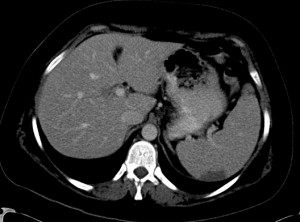

Splenic infarct in a patient with APLA syndrome